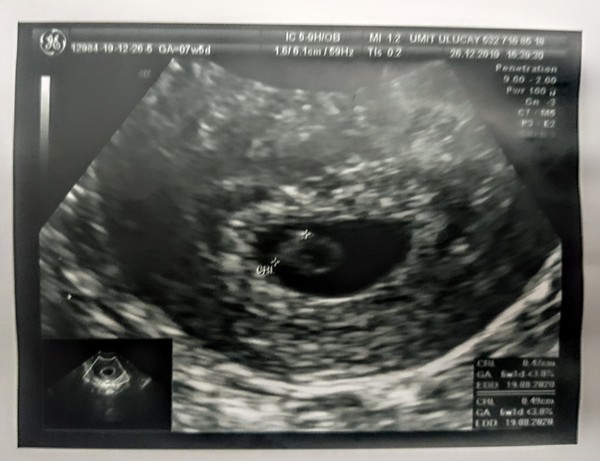

Went for an early scan last week thinking I was 7+5 ish (from my last LMP) but I have longer than average cycles and ovulated quite late so was actually only dated as 6+1....EDD 20/08/2020. I know early scans aren't always recommended but I'm in a LDR at the minute and really wanted OH to be at the first scan. Plus it really helped me to see our jelly bean and hear a strong heartbeat.

Early scan today at 8+1 and all looked fine. Saw the heartbeat - totally amazing.

All went well and saw a very wiggly baby with a good heartbeat, such a relief as just had no idea what may have been going on in then. My symptoms have generally eased as well so was a little panicky but all was looking good and baby like :-)

@Realladymarmalade you seem like you know already but I would definitely wait as long as you can, as I was IVF I knew my dates exactly but with natural if your dates are out you may not see enough if you go too early. It’s worth going just pick your time :-) I went 6+5 and you just get to see it’s viable with a heartbeat, by 9+5 I could see a lot more baby for money! I saw a baby wiggling with head and arms and a good heartbeat so was worth it for me. Appreciate 9 weeks is a long wait when you are 6 weeks so go with what will make you happy!

Hello everyone! Bit late to the board I know, only found out I was pregnant last Monday (the stress of christmas and 2 pre.school aged DC I didnt think about the fact I had missed my period) had a scan on Friday was lovely to see little bean heartbeat flickering away and all spot on with dates, am due 19th August excited and scared at the same time - also not enjoying the very sore boobs or constant nausea/sickness